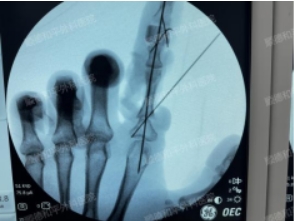

入院后,经过对手部和供区的检查评估,很快制定了一份精细的手指再造手术方案。手术当天,在超级显微技术下,手术团队默契协作,把握每一个细节,历经近7个小时手术顺利完成。

经过7天的卧床抗炎、抗凝、抗痉挛等护理治疗,可见再造手指红润饱满,顺利成活。而这不仅代表着身体上的变化,更意味着精神上的转变,重新找回了对生活的信念。

术后第8天